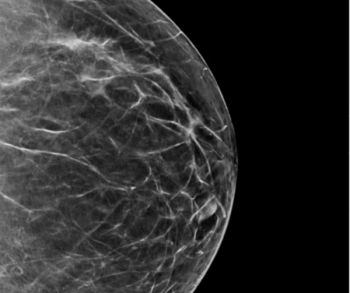

Comparing year-long findings with and without adjunctive artificial intelligence (AI) at a breast cancer screening program in Spain, researchers found the combination of digital breast tomosynthesis and AI had a 92.5 percent accuracy for diagnosing cancer in patients with elevated risk.